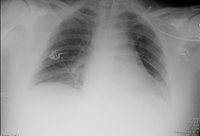

Portable chest x-ray with bibasilar opacities, worse on the right than the left, in a patient with hospital-acquired pneumonia

From the personal collection of Dr F.W. Arnold, Division of Infectious Diseases, Department of Medicine, University of Louisville School of Medicine